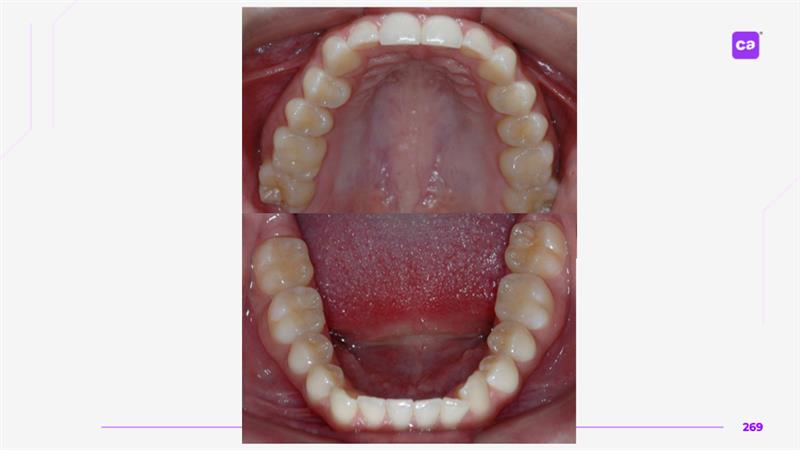

Figuras 4 – Fotos intraorais do caso clínico apresentadas em norma oclusal superior e inferior:

Na sequência apresentada, com os registros e comparação das fotos intraorais, observa-se a evolução do caso clínico desde a condição inicial até a finalização do tratamento com a conclusão do uso da série de alinhadores. Os resultados evidenciam a previsibilidade e acurácia do tratamento real em comparação às simulações e ao planejamento virtual inicial.

Observa-se a correção da sobremordida (mordida profunda), com avanço e torque vestibular dos incisivos superiores, juntamente com o nivelamento e alinhamento dentário das arcadas superior e inferior.

Além disso, nota-se o ajuste da linha média dentária superior, garantindo sua coincidência com a linha média inferior, bem como a otimização da curva e da estética do sorriso.